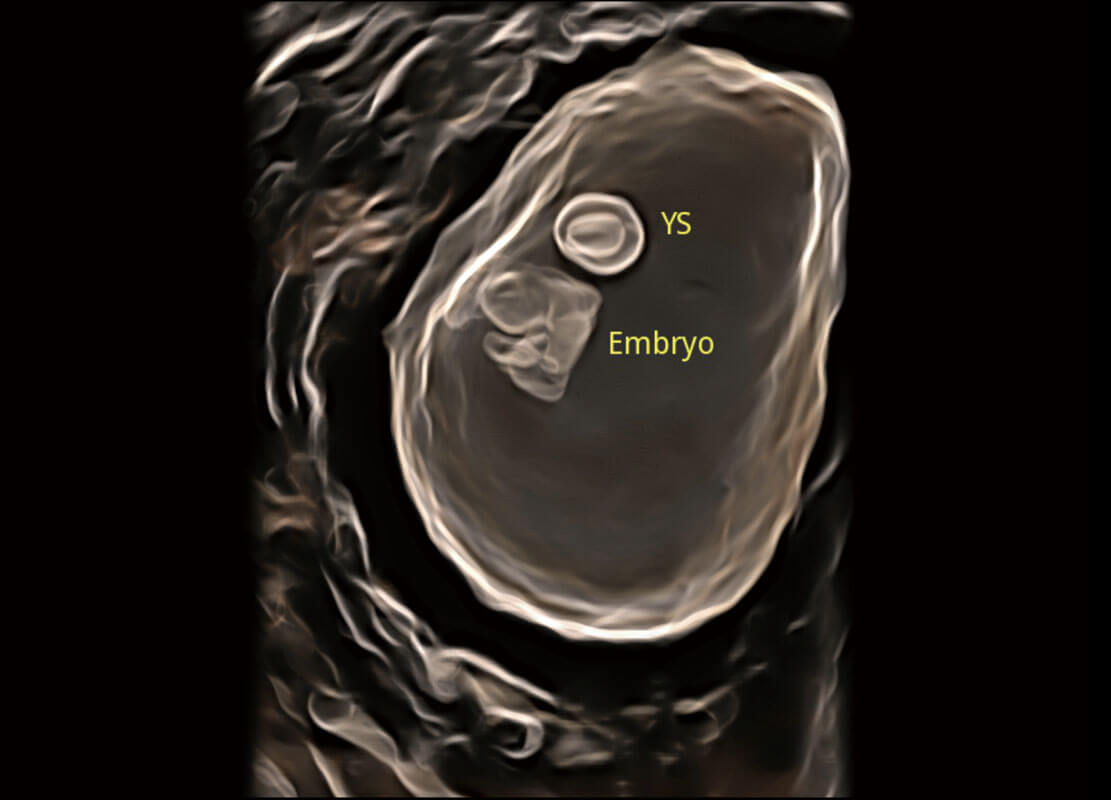

早孕筛查

P60在胎儿早孕期超声筛查中为您带来优异的图像质量。

• 光影成像-孕囊